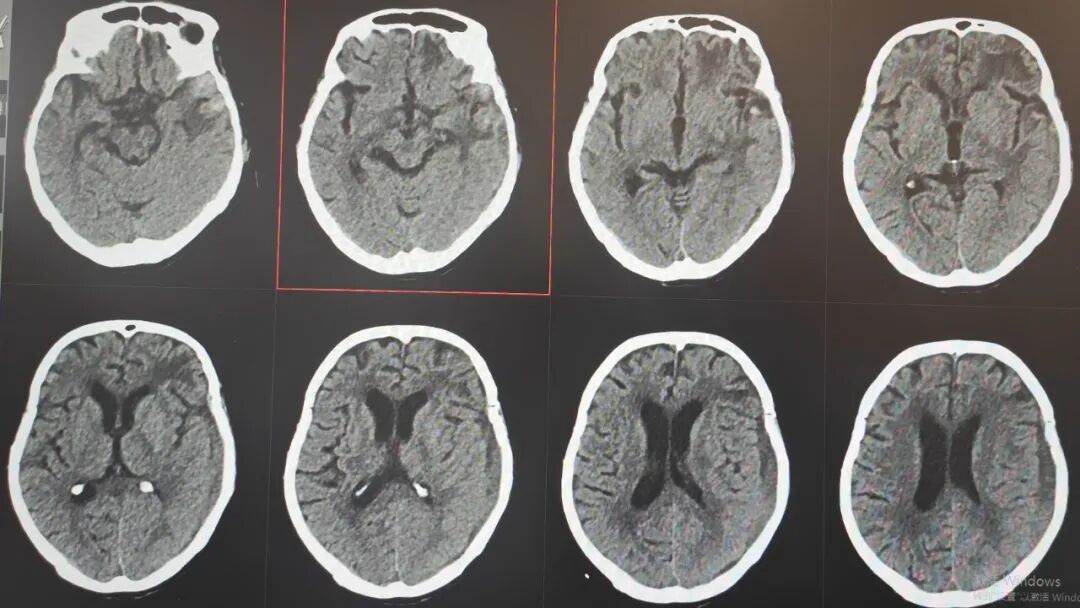

89 岁的吴阿婆(化名)突发意外,被发现时已意识不清、陷入昏迷。家人发现后,紧急将其送往漳州第三医院,检查结果令人揪心:重型颅脑损伤、脑内大面积出血,加之 O 型 Rh(D) 阴性熊猫血、严重贫血······多重致命高危因素叠加,病情十分危重。

那段日子,病情几度反复、险象环生,医护人员寸步不离守在床前,24 小时紧盯生命体征,精细调整每一步治疗方案,昼夜不敢有丝毫松懈。在一次次与死神的拉锯中,他们凭着耐心与坚守,终于等来了转机:阿婆从深度昏迷慢慢睁开双眼,从卧床不起到能在搀扶下缓缓起身,每一个微小的进步,都藏着无数个日夜的坚守与温暖,让绝境之中绽放出生命的微光。

如今,吴阿婆已顺利闯过最凶险的危险期,身体恢复良好,已经康复出院。